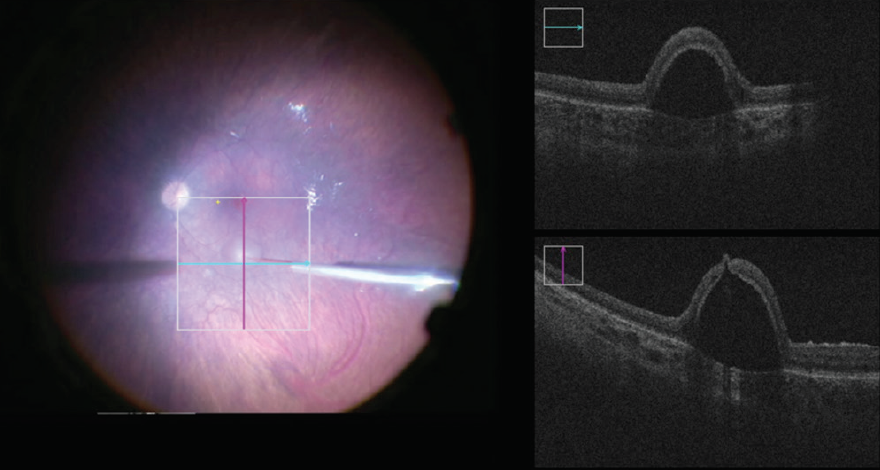

<p>Figure. Intraoperative OCT-guided subretinal injection of voretigene neparvovec-rzyl in a pediatric patient.</p>

Figure. Intraoperative OCT-guided subretinal injection of voretigene neparvovec-rzyl in a pediatric patient.

OCT Guidance

Although it is not essential, the use of OCT intraoperatively has been a great visual aid for determining the location of the bleb and status of the fovea. I deliver the vector with the two-line crosshair overlay on the ReScan microscope (Carl Zeiss Meditec; Figure). This has allowed me to better understand the importance of cannula positioning and to characterize some atypical bleb appearances (eg, schisis at the edge of the bleb).